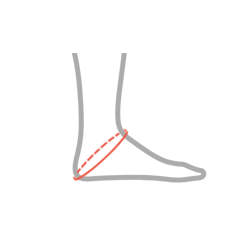

| Rozmiar | Obwód przez piętę | Sposób dokonywania pomiaru |

| S | 27 – 30 cm |  |

| M | 30 – 33 cm | |

| L | 33 – 36 cm | |

| XL | 36 – 39 cm | |

| 2XL | 39 – 41 cm |